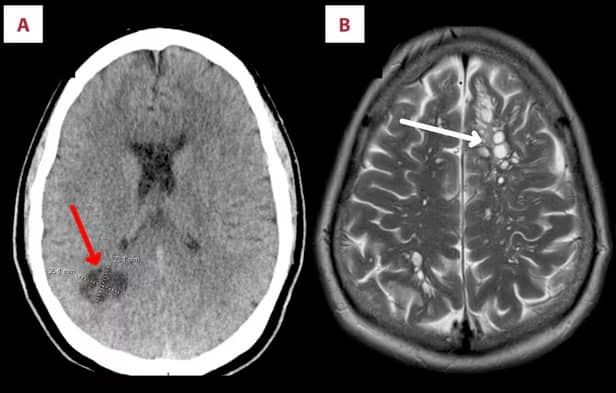

병원에서 A씨의 뇌 스캔 검사를 한 결과, 의료진은 충격적인 진단을 내렸습니다.

"뇌에 침투한 기생충에 의한 두통 증상"

A씨의 뇌 양쪽에서 여러 개의 낭종(주위 조직과 뚜렷이 구별되는 막과 내용물을 지닌 주머니)이 발견됐고 낭종 주변으로는 뇌가 부어 있는 상태였습니다.

의료진은 이를 기생충 감염에 의한 신경낭미충증(Neurocysticercosis) 이라고 진단했는데, 바로 돼지 촌충이 뇌에 알을 낳고 알에서 나온 총충이 두개골 조직을 자극해 두통이 유발된 것입니다.

의료진은 A씨에게 뇌부종을 가라앉히고 기생충을 없애기 위해 약물을 투여했고, 다행히 A씨 뇌 속 낭종은 2주 만에 사라졌다고 전했습니다.